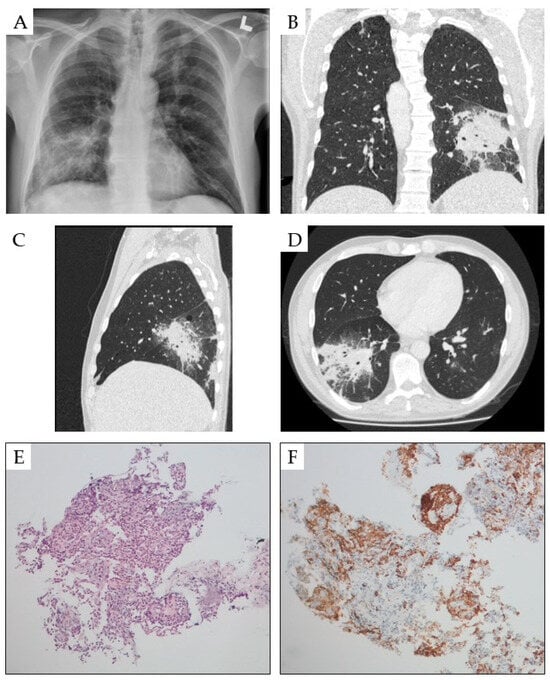

4. Pulmonary Symptoms

- Ecsiova, D.; Kamaradova, K.; Nova, M.; Hoffmann, P.; Rozsivalova, P.; Simkovic, M.; Zak, P. Pulmonary damage in a patient with hairy cell leukemia-infectious involvement or hematological disease activity? Case report. Biomed. Pap. Med. Fac. Univ. Palacky. Olomouc Czech Repub. 2023, 167, 385–389. [Google Scholar] [CrossRef]